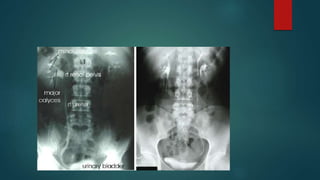

Renal important spotter

Renal tb